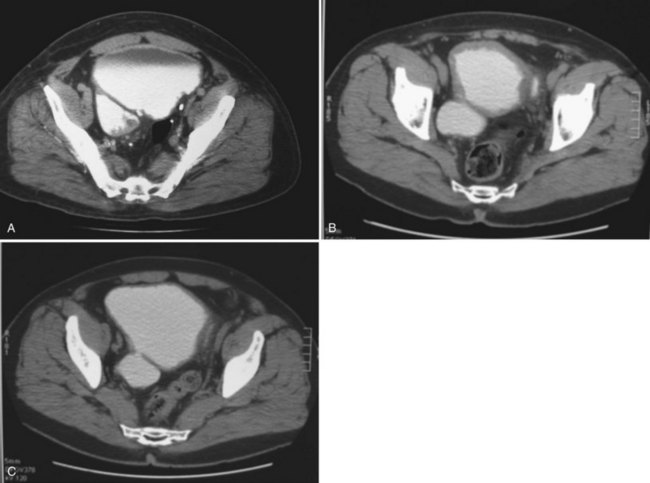

If the neck of the diverticulum is obstructed from a tumor or otherwise not patent, cross-sectional imaging may be required for diagnosis (Dondalski et al, 1993). Cross-sectional imaging, including computed tomography (CT) and magnetic resonance imaging (MRI) may also be useful for the evaluation of masses within the diverticulum (see under Associated Conditions). Review of the radiographic films should accurately characterize the number, anatomy, and location of the diverticula. Filling defects within the diverticula or other bladder abnormalities should prompt further investigation (Fig. 78–4).

Figure 78–4 CT scans demonstrating several abnormalities in the setting of a bladder diverticulum. A, Diverticulum with multiple filling defects. Cystoscopy and biopsy revealed transitional cell carcinoma. B, Diffusely thickened and irregular bladder wall due to chronic bladder outlet obstruction in association with two diverticula. Cystoscopy confirmed trabeculation without mucosal abnormalities. C, Asymmetric bladder wall thickening in association with a bladder diverticulum. The ostium of the diverticulum is seen connecting to the bladder.